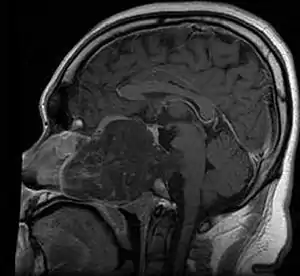

.jpg.webp)

Chordomas can arise from bone in the skull base and anywhere along the spine. The two most common locations are cranially at the clivus and in the sacrum at the bottom of the spine.[2]